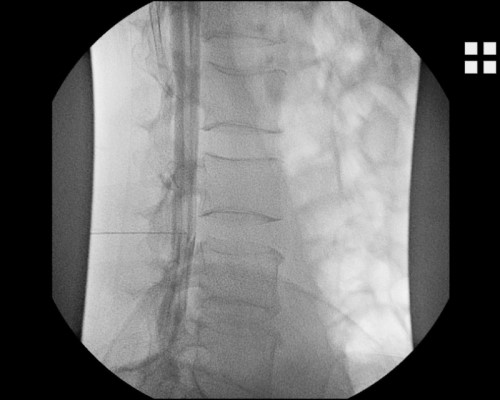

Die Myelographie bzw. Myelografie ist ein bildgebendes Verfahren, bei dem ein Kontrastmittel in den das Rückenmark (griechisch Myelon) enthaltenden Wirbelkanal (genannt auch Rückenmarkskanal) gespritzt wird und anschließend eine Röntgenaufnahme durchgeführt wird.

Vor der Entwicklung der als „Großradiologie“ bezeichneten Computertomographie (CT) und Kernspintomographie (MRT) war es schwierig, Bandscheibenvorfälle und andere Raumforderungen im Wirbelkanal zu beurteilen. Die Myelografie bietet eine Möglichkeit der weiterführenden Diagnostik. Zwischen den Wirbelbögen des dritten und vierten Lendenwirbels wird eine Spezialkanüle eingeführt (Lumbalpunktion), die bis in den Duralsack (Liquorraum) reicht. Die Lage ist dann korrekt, wenn Rückenmarksflüssigkeit aus der Kanüle tropft. Walter Dandy berichtete 1925 über erste Erfahrungen mit der Luftmyelographie. In Deutschland wurde die Myelographie insbesondere nach den umfassenden Forschungsarbeiten von Herbert Peiper eingeführt, der dieses Forschungsthema in seiner Habilitationsarbeit Die Myelographie im Dienste der Diagnostik von Erkrankungen des Rückenmarks 1926 bearbeitete.

Bei spinalen Wurzelkompressionssyndromen kann in einer Myelographie der Vorteil der dynamischen Aufnahmemöglichkeit genutzt werden, um Füllungsdefekte der sogenannten Wurzeltaschen nachzuweisen. Daher dient die Myelografie präoperativ zur Klärung offener Fragen, wenn ein MRT oder CT nicht oder nicht artefaktfrei (z. B. bei Skoliose) durchgeführt werden können.

Nach Kontrastmittelgabe und Myelografie kann auch eine CT angefertigt werden, um zusätzlich Schichtbilder unter Kontrastmittelgabe zu erhalten.